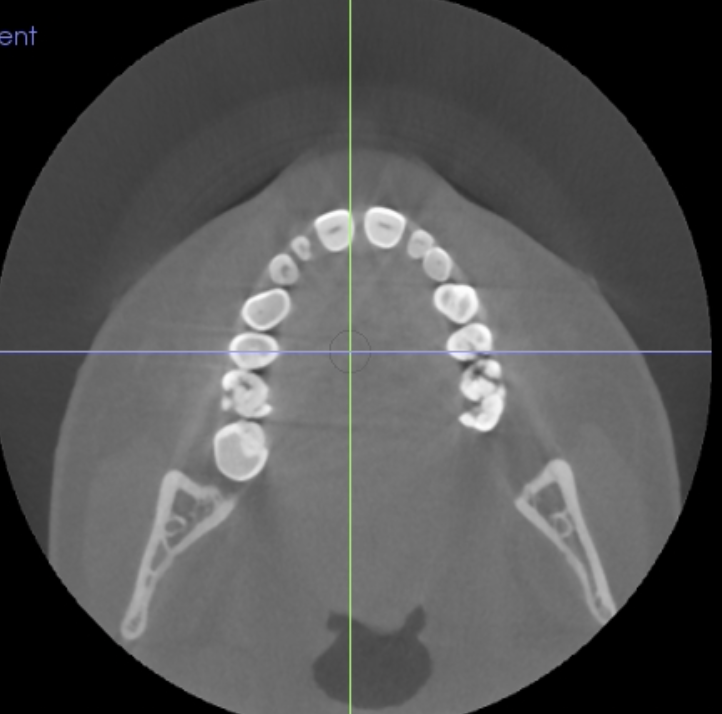

Q

Axial

9

Coronal